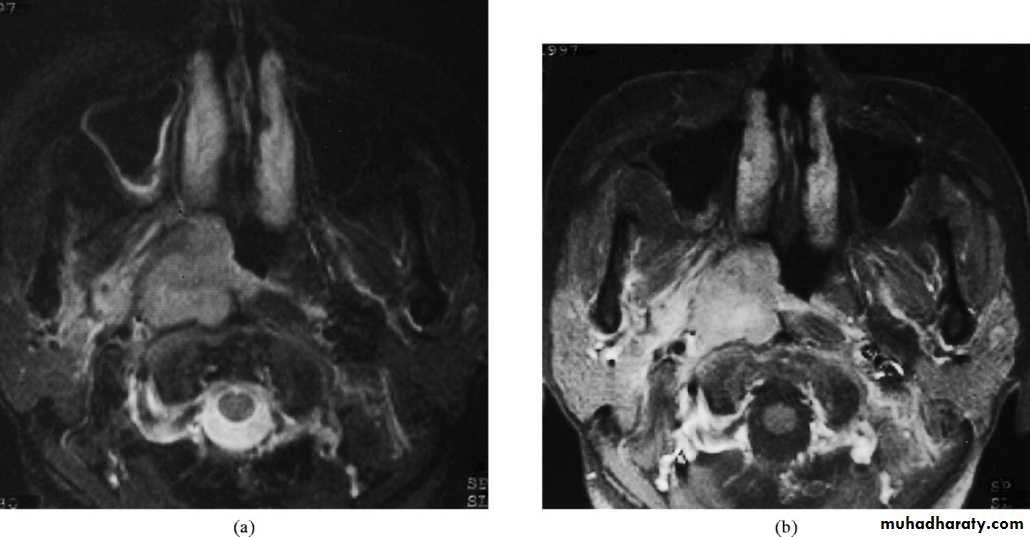

b. CAT scan, MRI and MRA.

1. Imaging:

a. X-ray of the base of the skull---- bony destruction involving the petrous bone, foramen lacerum and carotid canal.

b. CT scan and MRI: MRI is superior to CT scan in finding soft tissue involvement.